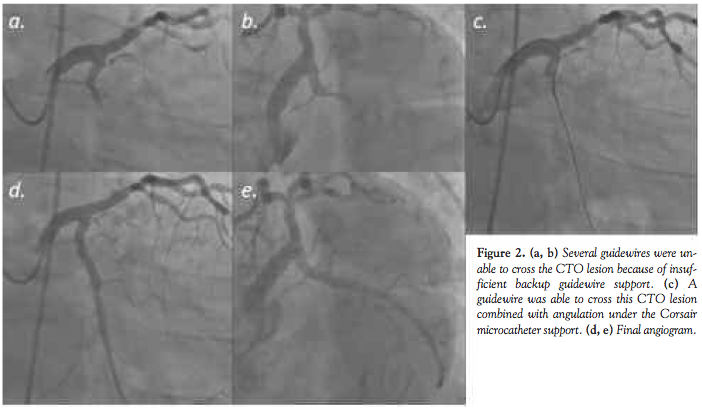

or a 7 Fr BLH Brite tip guiding catheter (Cordis) was used via the right femoral artery. We tried to proceed the Finecross microcatheter, (Terumo) to the completely occluded LCx artery using a Rinato guidewire (Asahi Intecc), but multiple attempts to deliver the micro-catheter to the LCx occlusion were unsuccessful due to the prolapse of microcatheter into the patent left anterior descending (LAD) artery (Figures 1c and d). The extremely steep angle of LCx artery in its take-off from the very large left main trunk seemed to the cause of the difficulty to advance the microcatheter. To take more co-axial direction to the LCx artery, the guiding catheter was changed to a 6 Fr Amplatz 3.0 Heartrail guiding catheter. Then, an X-treme guidewire (Asahi Intecc) was used to select the atrial branch for a Finecross micro-catheter delivery (Figure 1e) and the Finecross micro-catheter could successfully cross the steep angle of LCx artery (Figure 1f). Subsequently, an X-treme guidewire and the Finecross micro-catheter were further advanced toward the proximal part of the CTO lesion. A Wizard 3 (Japan Lifeline), a Miracle 6, and a Conquest Pro guidewire (Asahi Intecc) were used to cross this CTO lesion but were unsuccessful because of insufficient backup guidewire support (Figures 2a and b). Therefore, we changed the micro-catheter to a Corsair micro-catheter. A Corsair micro-catheter was easily advanced toward the just proximal part of the CTO lesion using a similar method. Finally, the Conquest Pro guidewire (Asahi Intecc) was able to cross this CTO lesion (Figure 2c). Although a Corsair micro-catheter was not able to cross this CTO lesion, a 1.25-mm x 10-mm Tazuna balloon (Terumo) was able to cross and successfully dilated the CTO lesion. A 2.5-mm x 15-mm Signet Pro balloon (St. Jude Medical) was then used to open this CTO lesion further. Stent implantation was successfully performed using a 3.5-mm x 23-mm Xience V stent (Abbott). Final coronary angiogram showed a satisfactory result without any complications (Figures 2d and 2e).